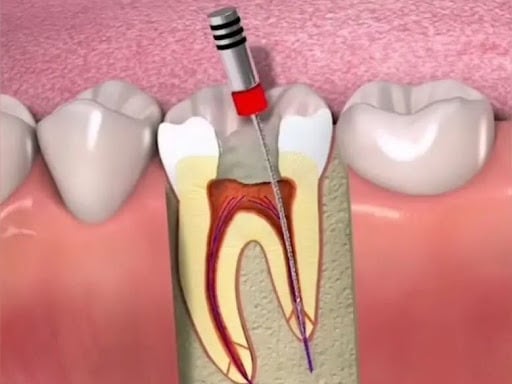

Es un procedimiento en el que se abre la cámara pulpar del diente para eliminar el tejido pulpar infectado o inflamado. Esto ayuda a aliviar el dolor y preparar el diente para un tratamiento de conducto.

Trepanación Pulpar (urgencia)

Es el procedimiento para limpiar, desinfectar y sellar los conductos internos del diente cuando la pulpa está infectada o inflamada. Es esencial para salvar el diente.

Tratamiento de Conducto